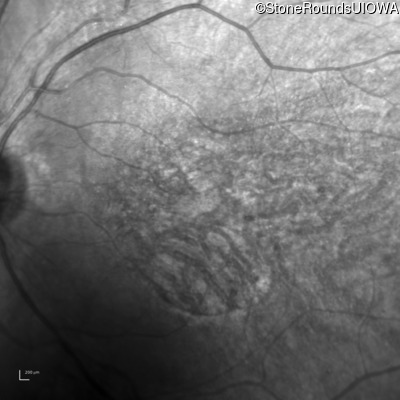

AD Retinitis Pigmentosa (IA1aii)

Age at visit: 60 years

This 60 year old woman first noticed difficulty reading the newspaper about 1 year ago. She also noticed worsening photophobia about that time.

AD Retinitis Pigmentosa PROM1 Arg373Cys CGC>TGC   AD